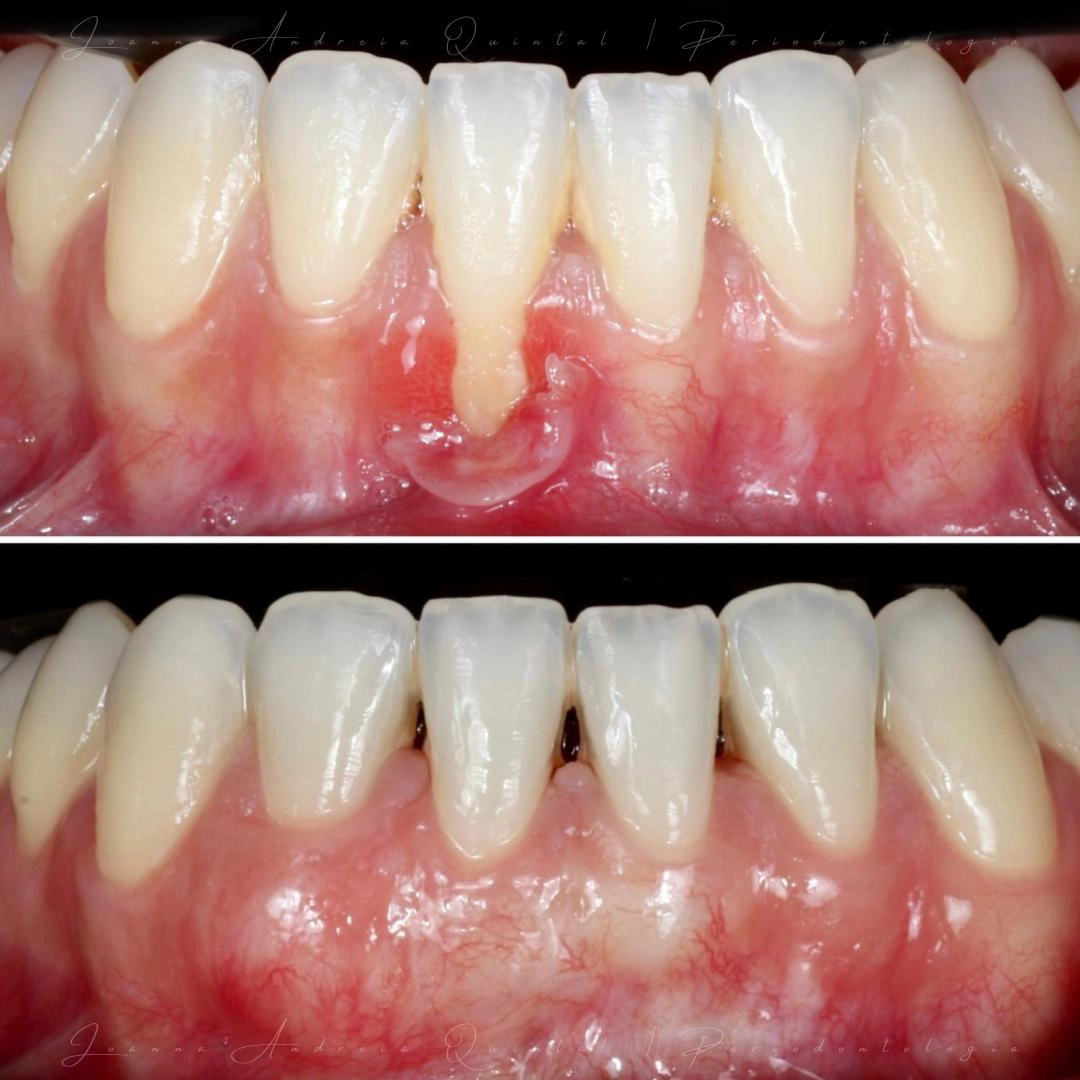

A saúde dos tecidos de suporte — gengiva e osso — é essencial para a estabilidade e longevidade de qualquer tratamento dentário. Nesta área, avaliamos e tratamos a doença periodontal com rigor clínico, promovendo controlo da inflamação e equilíbrio biológico. Uma base saudável é fundamental para resultados previsíveis.

Uma seleção de casos que mostram a evolução clínica real. Cada transformação reflete o nosso compromisso com precisão, naturalidade e cuidado personalizado.